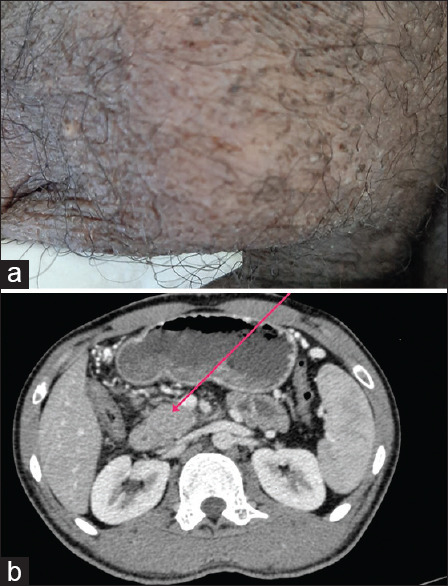

我们描述了一名患者,他在局部创伤后出现阴囊肿胀,随后阴囊窦不愈合并排出,最初被怀疑有感染性阴囊血肿。评估显示是阴囊结核。他还抱怨上腹部疼痛,经腹部超声检查发现胰头有肿块。胰腺肿块的评估显示是胰腺结核。两种病变对抗结核治疗反应良好。这是一个罕见的肺外结核两个罕见部位同时出现在同一个人身上的病例。在结核病流行国家,在评估任何无法愈合的溃疡、鼻窦和肿块时,都需要小心,因为这种疾病可能是一种很好的伪装。

We describe a patient who presented with scrotal swelling followed by non-healing and discharging scrotal sinuses, following local trauma and was initially suspected to have an infected scrotal hematoma. An evaluation revealed it to be scrotal tuberculosis. He also complained of upper abdominal pain and on transabdominal ultrasonography was detected to have a mass in the head of the pancreas. Evaluation of the pancreatic mass revealed it to be pancreatic tuberculosis. Both lesions responded well to anti-tubercular therapy. This is an unusual case of two rare sites of extrapulmonary tuberculosis presenting simultaneously in the same individual. Care needs to be exercised while evaluating any non-healing ulcers or sinuses and mass lesions in countries endemic for tuberculosis as this disease can be a great masquerader.